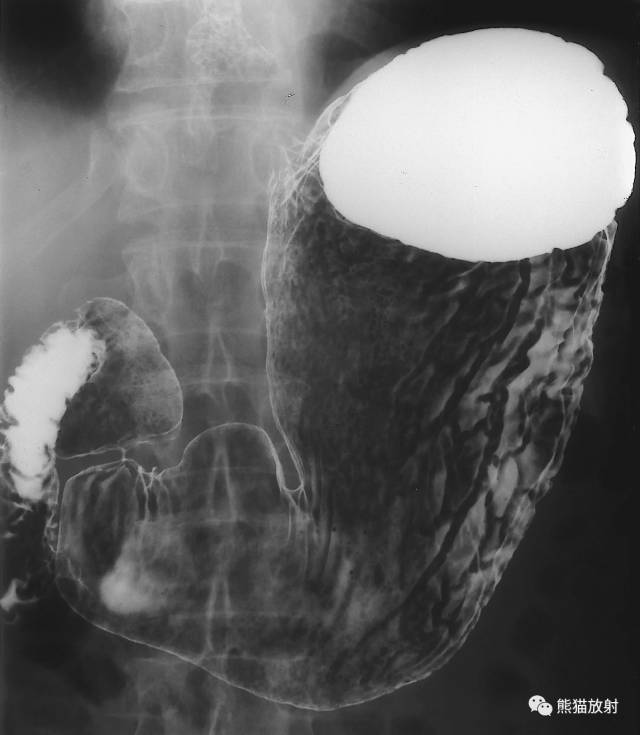

5 Stomach 胃

1 Fundus 底,2 Abdominal esophagus 腹段食管,3 Cardia 贲门,4 Lesser curvature 小弯,5 Duodenum 十二指肠,6 duodenal bulb 十二指肠球部,7 Gastric folds (posterior wall) 胃皱襞(后壁),8 Pylorus 幽门,9 Body of the stomach 胃体,10 Angular notch 角切迹,11 Greater curvature 大弯,12 Pyloric antrum 幽门管,12 + 13 Antrum 胃窦